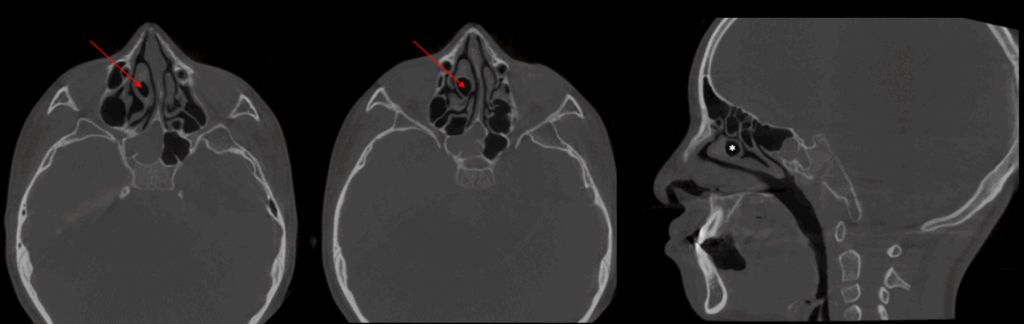

A la evaluación de la tomografía volumétrica (cone beam) de macizo facial en los cortes coronales (Figura 2), axiales y sagital (Figura 3) se observa el defecto óseo que se extiende desde la cima del reborde alveolar hasta el piso de la fosa nasal del lado izquierdo comprometiendo ambas estructuras, desviación del tabique hacia lado izquierdo y neumatización del cornete medio de lado

derecho,

CORTES AXIALES Y SAGITALES

En la reconstrucción 3D de tejidos blandos se observa la fisura alveolo palatanila unilateral y la presencia de concha bullosa de cornete medio de lado derecho